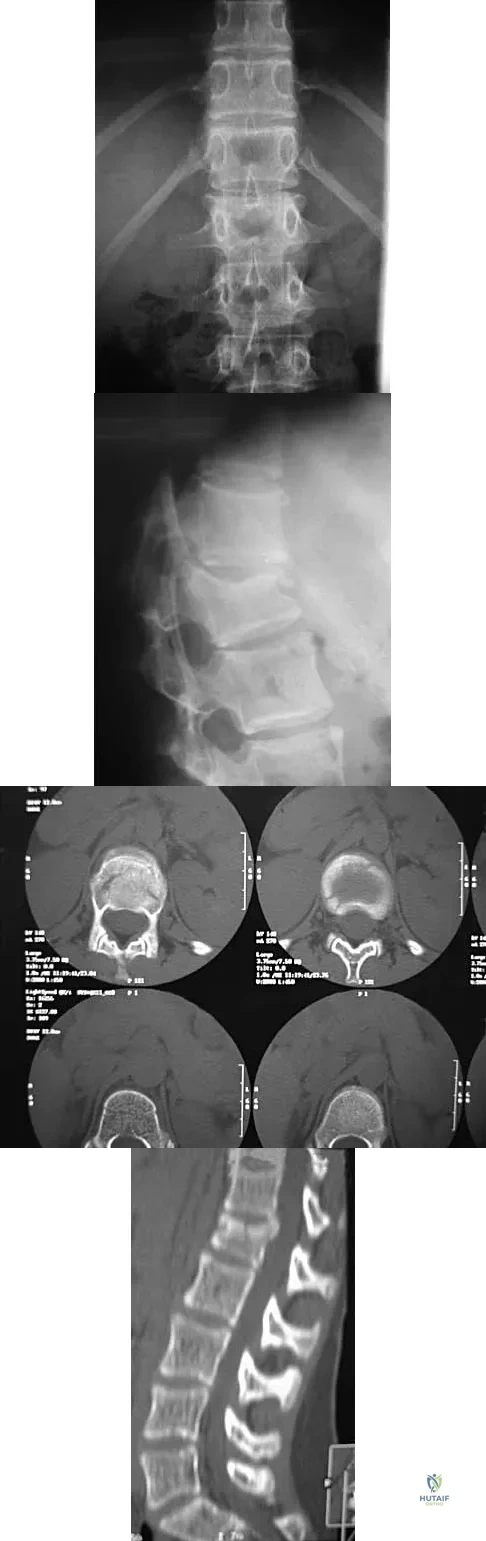

Question 54

A 19-year-old man has had back pain with activity, especially running in soccer and baseball, for the past 4 months. He denies any history of trauma. Examination reveals no motor weakness or sensory changes in the lower extremities. Range of motion shows increased pain with extension and mild limitation with flexion. A sitting straight leg raising test is limited at approximately 60 degrees bilaterally by back and buttocks pain. Plain radiographs are normal. MRI scans are shown in Figures 13a through 13e. What is the most likely diagnosis?

Explanation